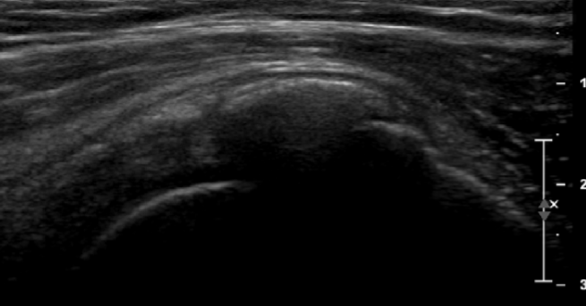

V kolikor so kalcinati večji od 8mm in so enakomerne strukture lahko pod ultrazvočno kontrolo opravimo tudi punkcijo kalcinata in kalcinat izperemo. Poseg se opravi v lokalni anesteziji in traja približno 30 minut. Bolečina lahko traja tudi nekaj dni po posegu. V teh primerih svetujemo jemanje analgetikov. Nekaj dni po posegu priporočamo postopno stopnjevanje aktivnosti, izvajanje vaj, plavanja, nordijske hoje in fizikalne terapije in po 2 -3 mesecih vrnitev željenim aktivnostim.